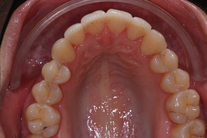

Ung kvinna som tidigare haft tandreglering. Upplever inte att tänderna står i en fin tandbåge. 11 månaders behandling med genomskinliga Invisalignskenor resulterade i ett fint leende.